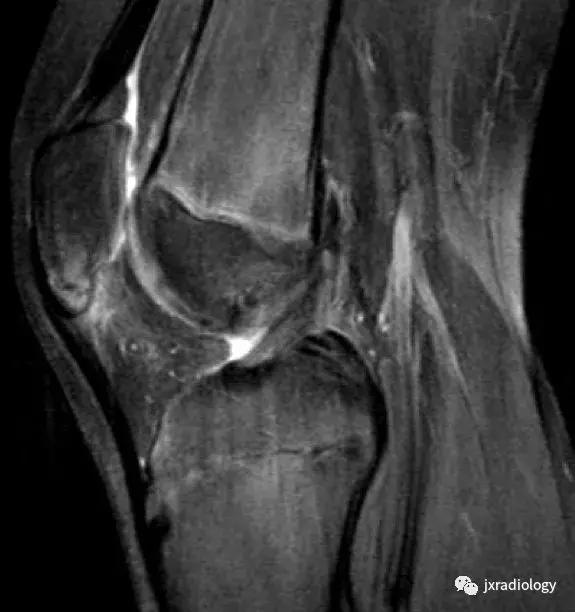

图18:剥脱性骨软骨炎(OCD)。 OCD的病因学是未知的,可能是多因素的,包括损伤,血管因素,压力变化,发育差异和遗传学等。 膝关节OCD最常见的部位是股骨内侧髁(75%)。 这里显示了特征性的MRI表现,通常没有其它的损伤:在骨软骨碎片周围(b)有明显的小片骨髓水肿。 (a,b:冠状T1-WI和冠状PD-FS-WI)。